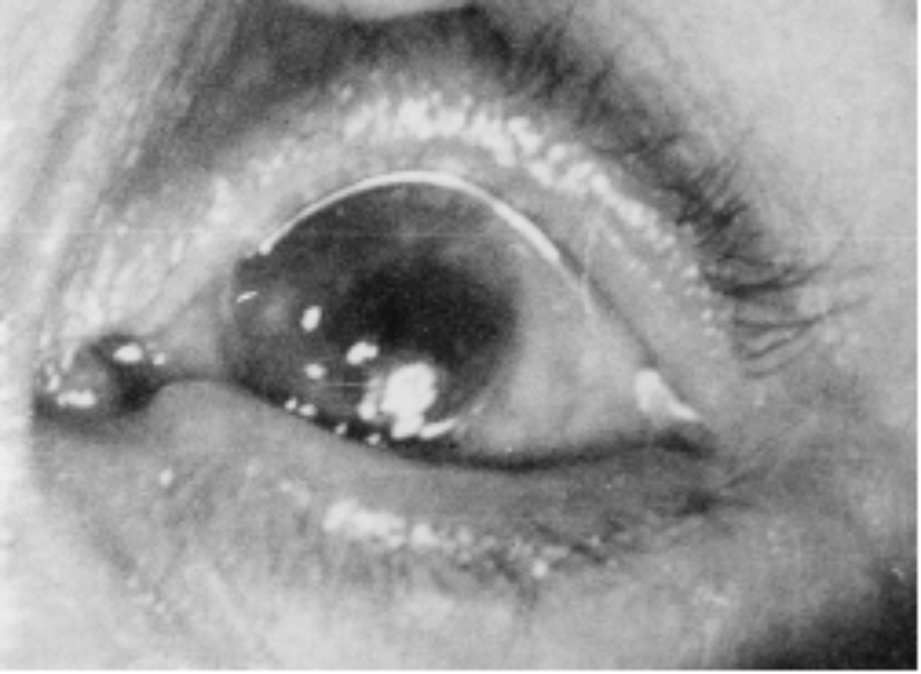

移植片的转归;10例中,术后1个月~1年植片透明愈合1例,半透明4例,混浊3例,植片脱落2例。随访5~8年植片半透明4例,混浊6例(其中植片有新生血管2例,脱落2例包括在内)。视力:10例中,出院时视力较术前提高3行以上或从眼前手动、指数提高到0.1以上者3例,无变化7例;随访4个月~8年视力提高3行以上或从眼前手动、指数提高到0.1以上者3例,无变化6例,有1例植片由透明变成混浊,视力由出院时0.5下降到眼前手动(见附录部分病例彩色图片)。

附 录

鹅角膜板层移植部分病例

第一例